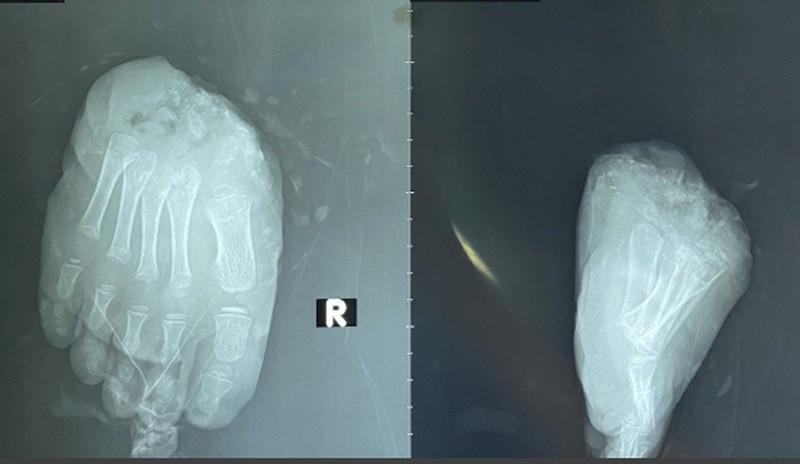

Ảnh chụp phim ghi nhận bệnh nhi bệnh nhi bị đứt lìa ngang qua 2/3 trước bàn chân lộ gân xương.